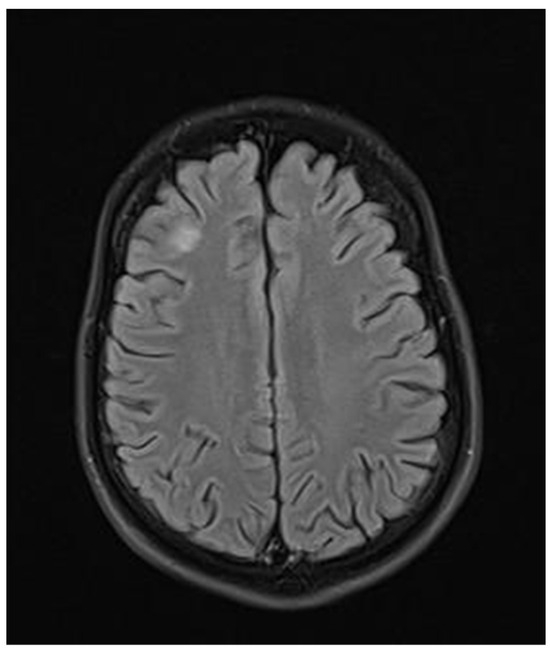

ADEM recurrence was recognized. The patient received immunoglobulins (2.0 g IV). After rehabilitation, an improvement in the neurological condition was observed over the next four weeks. The boy returned to school. Subsequently, he reported visual acuity disturbances in the left eye. Therefore, he was hospitalized in the neurology department. On admission, neurological examination showed horizontal nystagmus, lack of abduction in the right eye, dysarthric speech, and cerebellar syndrome. Brain MRI revealed numerous foci of increased signal on T2-weighted and FLAIR sequences, with the largest one occurring in the right cerebellar hemisphere accompanied by the involvement of the peduncle (Figure 5 and Figure 6) and bilateral involvement of the dentate nuclei of the cerebellum. Foci of increased signals on T2-weighted and FLAIR sequences were also found on MRI of the cervical and thoracic spine, meeting the LETM (longitudinally extensive transverse myelitis) criteria (Figure 7). Moreover, an orbital MRI showed “the left optic nerve was thickened to 3–4 mm, with increased T2 signal intensity indicating inflammation; the optic chiasm and right optic nerve were normal” (Figure 8). Again, positive serum anti-MOG antibodies were found in a clear titer of 1:100, while anti-AQP4 antibodies tested negative. Recurrent MOGAD was diagnosed based on the overall picture, and immunoglobulins were administered (a total dose of 2.0 g IV for five days). Oral azathioprine was included in the chronic treatment at a dose of 2 mg/kg body weight and oral methylprednisolone at a dose of 1 mg/kg body weight. After ten weeks (May 2022), right optic neuritis occurred during an attempt at withdrawing glucocorticosteroids. Methylprednisolone was reintroduced at a dose of 5 × 1.0 g intravenously. An MRI of the head revealed two new subcortical foci: one located in the right frontal lobe measuring 13 × 7 mm and another in the left parietal lobe measuring 19 × 14 mm (Figure 9). Additionally, the right optic nerve exhibited blurred outlines (Figure 10) and an increased signal in the central area, along with a marginally enhancing focus in the middle part of the right optic nerve measuring 2 mm in diameter. An ophthalmological consultation was conducted, revealing color vision deficiencies in the right eye across all axes, with no reading capability in the left eye. An OCT examination showed that the retinal nerve fiber layer (RNFL) in the right eye was normal (higher than a month earlier, suggesting a possible inflammatory process), while the left eye exhibited significantly reduced RNFL and ganglion cell count. Atrophy of the left optic nerve was diagnosed. Based on the clinical presentation, recurrent optic neuritis was diagnosed as a manifestation of another MOGAG, correlating with the onset of right optic neuritis following the discontinuation of methylprednisolone. Therefore, a decision was made to increase the dose of azathioprine to 2.5 mg/kg body weight and to maintain methylprednisolone for the following weeks. After the diagnosis of MOGAD with a typical radiological and clinical picture (ADEM, MDEM, recurrent ON) and the initiation of chronic immunosuppressive treatment, no more epileptic seizures were observed. It was decided to discontinue antiepileptic drugs, starting with gradual valproic acid.

Figure 9.

Transverse FLAIR brain magnetic resonance image showing two new subcortical foci of increased signals: one located in the right frontal lobe measuring 13 × 7 mm and another in the left parietal lobe measuring 19 × 14 mm. (May 2022).